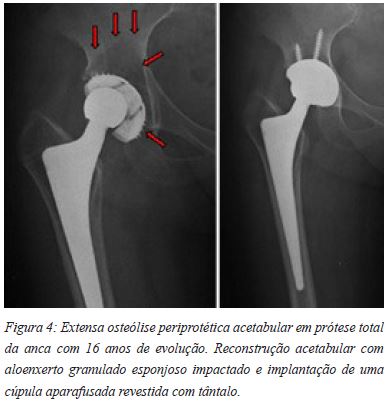

Desta forma, é possível dispor de uma quantidade substancial de aloenxertos provenientes de um só dador, não só do tipo esponjoso como também de aloenxertos estruturais de todos os tipos, formas e dimensões, com as vantagens daí decorrentes. A não ser assim, teríamos que usar várias cabeças femorais provenientes de diferentes dadores vivos, situação que devemos evitar sempre que tal seja possível. Por outro lado, a metodologia descrita facilita a disponibilização de unidades individuais de enxertos esponjosos, não havendo necessidade de libertar um dos elementos da equipa cirúrgica para a sua preparação no decurso da operação cirúrgica. Por último, importa dizer que o protocolo do processamento dos enxertos esponjosos foi validado pelos resultados de estudos experimentais6. Por sua vez, a sua utilização em recolocações de cúpulas acetabulares tem vindo a mostrar, ao longo dos últimos vinte e sete anos, resultados conseguidos (Figuras 4 e 5) no que toca à segurança microbiológica, comportamentos biológico e mecânico dos enxertos7,8.